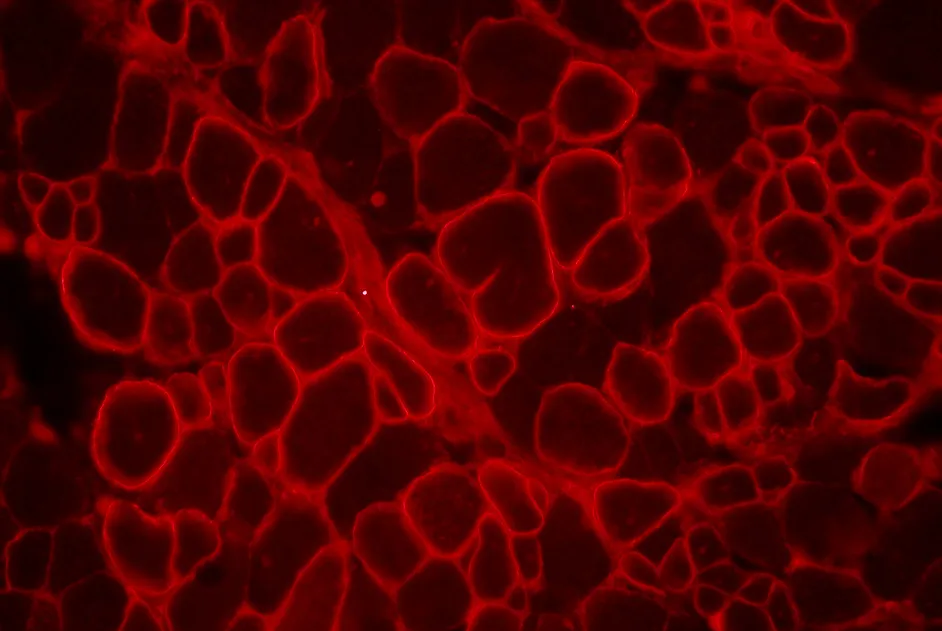

Une équipe américaine a mis en évidence l’efficacité d’un nouveau composé de translecture de codon stop, RTC13, dans des souris mdx.

Une équipe française, soutenue par l’AFM, a développé un nouveau modèle de myopathie de Duchenne, avec fibrose : la souris fib-mdx.